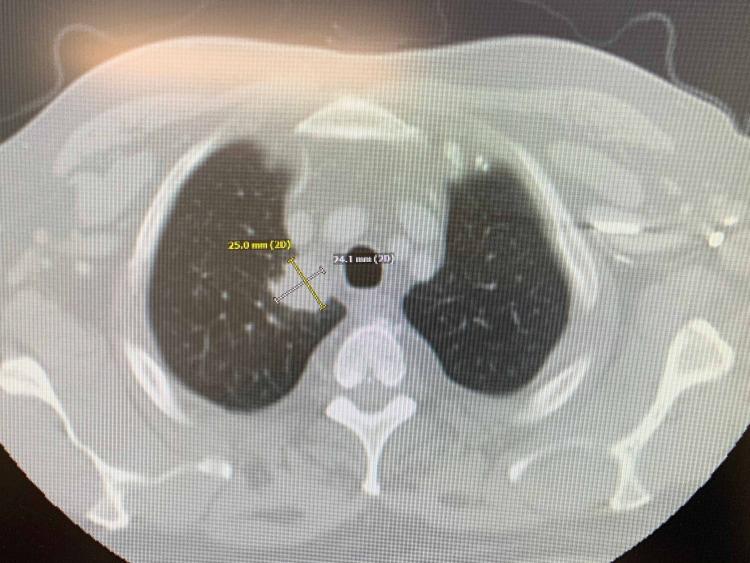

Pembrolizumab is an immune checkpoint inhibitor approved for use in many cancer types such as non-small cell lung cancer (NSCLC), metastatic melanoma, head and neck cancers, hepatocellular carcinoma, and renal cell carcinoma. There are many reported cases of patients on immunotherapy who have discontinued treatment due to the development of immune-related adverse effects (irAE). Recognition of the histopathologic patterns of dermatologic toxicities due to immunotherapy will become increasingly important for ensuring appropriate management and optimal patient care. Here, we present a case of a 72-year-old man with metastatic carcinoma of unknown primary origin treated with pembrolizumab who developed an immune-related cutaneous adverse event (ircAE) in the form of lichenoid dermatitis.

帕博利珠单抗是一种免疫检查点抑制剂,已被批准用于多种癌症类型,如非小细胞肺癌(NSCLC)、转移性黑色素瘤、头颈癌、肝细胞癌和肾细胞癌。有许多关于接受免疫治疗的患者因出现免疫相关不良反应(irAE)而停药的报道病例。认识免疫治疗引起的皮肤毒性的组织病理学模式对于确保适当的管理和最佳的患者护理将变得越来越重要。在此,我们报告一例72岁男性患者,其原发灶不明的转移性癌接受帕博利珠单抗治疗后出现了苔藓样皮炎形式的免疫相关皮肤不良事件(ircAE)。